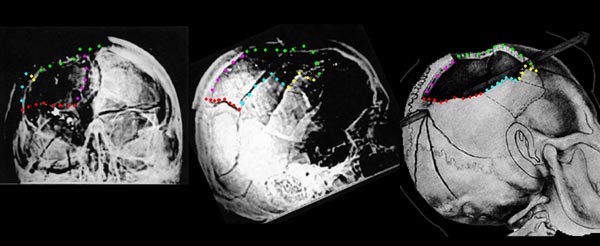

That's what "photo experts" like Robert Groden (in The Killing of a President, page 81) and Harrison Livingstone (in High Treason II) do. Wanting to show the back of Kennedy's head blown out — and thus push the notion of a Grassy Knoll shooter — they use a close-up autopsy photo of the inside of Kennedy's skull after the brain was removed. By rotating the photo ninety degrees clockwise, they can make it appear that the photo shows a large defect in the back of Kennedy's head. In actuality, Kennedy was photographed from the front, and the photo shows the top if his head blasted out, as shown in this drawing by Dr.

Robert Artwohl. Finally, a large and properly-oriented copy of the head photo.

I rotated the drawing and drew a yellow line to mark the entrance wound location and green lines to mark the upper and lower boundaries of the skull defect. These match up quite well.

My own interpretation is below. Although it is not a perfect match, it is fairly close.

Vergleich mit der Perspektive der Hinterkopffotos